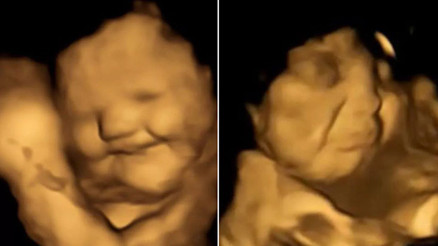

#BeslenmeÇocuklara sağlıklı beslenme alışkanlıkları kazandırmak, özellikle de sebze tüketimini teşvik etmek, ebeveynler için sonu gelmeyen bir mücadele. Yakın zamanda yapılan bir araştırma ise çocuklara sebzeyi sevdirmenin yolunun anne karnından geçtiğine işaret ediyor. İşte detaylar…